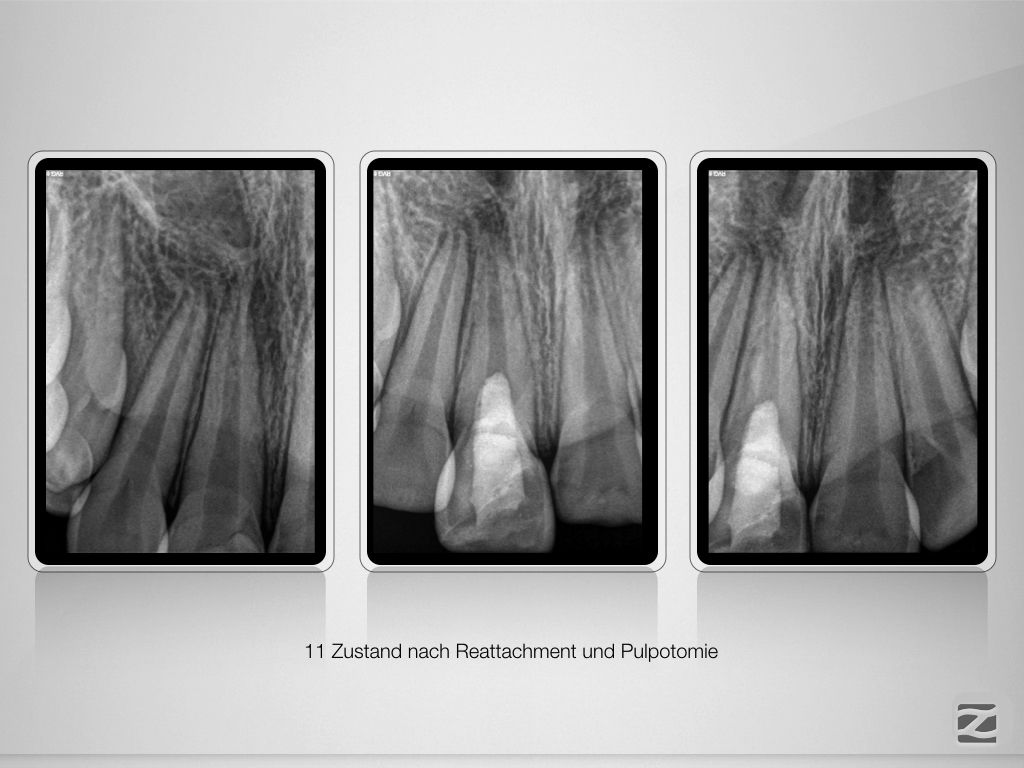

Frontzahntrauma – erstes Recall